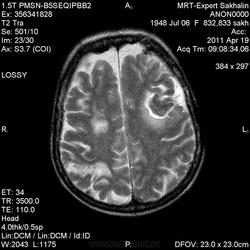

склоняюсь к кровизлиянию в левой теменной долей, начало перехода острой стадии в раннюю подострую( по периферии определяется повышение МРС по Т1 ВИ -метгемоглобин). Справа -старые кортикальные постишемческие глиозно-атрофические изменения. Контрастируется , вероятно за счет формирования участков ангионеогенза.

Это демиелинизирующий процесс, острая стадия, причем с геморрагическим пропитыванием в центре пораженных участков. В принципе, соответствует тяжелому рассеяному склерозу, хотя может быть и геморрагическая форма ОДЭМ. Также могут быть мозговые проявления системного васкулита: надо знать анамнез.

На фоне ДЭП изменений МР-картина ОНМК по ишемическому типу в бассейне ЛСМА с участками геморрагического пропитывания. Аналогичный участок но в более поздней фазе в задних конвнкситальных отделах правой теменной доли.

О.С., я согласен, что контрастирование нехарактерно для ОНМК, ведь в подострую стадию инфаркта наблюдается, как правило, гиральный тип усиления. Плюс, на ОНМК непохоже то, что поражено почти только белое вещество, а кора интактна. И потом, при такой локализации инфаркта обязательно должна быть яркая клиника, и уж никак не только "головная боль".

А средний мозг ?Там тоже очаги гиперинтенсивного по Т2сигнала.

Что касается снимочков мне кажется что зона патологического сигнала в левой гемисфере можно расценить как подострую стадию ОНМК с геморрагическим пропитыванием, справа как последствия ОНМК. При чем множественные очаги скорей всего как проявление ХМНК. И обязательно рекомендовать контрольное МРТ в динамике . Если это действительно ОНМК на фоне лечения отек уйдет и будет формированиться зона кистозно-глиозных изменений, а если отек будет нарастать значит надо думать о объемном процессе.